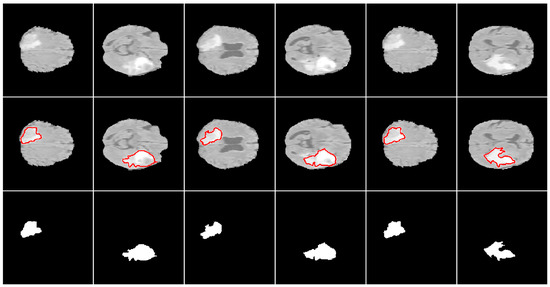

3.2.2. Comparison of Different Loss Functions

We observed that the Adam optimizer performed best in the tumor segmentation task. As such, we tested its performance on different loss functions with all four MRI modalities of the original dataset provided as different input channels. Table 2 shows the results (mean and standard deviation of a five-fold cross validation). Figure 6 shows some 2-D segmentation results along with their segmentation boundaries and segmented regions. Similar to previous studies where the segmented region was small with respect to the background [53], the Dice loss function performed best. The 3-D methods showed more precise results than their 2-D counterparts, likely because volumetric data retain 3-D information that is lost when using 2-D slices separately as input.

Figure 6. Example 2-D segmentation results. From top to bottom: input images, segmentation boundaries, and segmented regions.